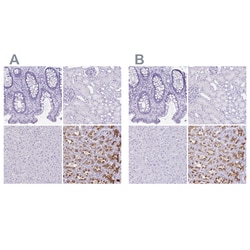

Invitrogen™ ATP4B Polyclonal Antibody

Brand: Invitrogen™ PA583771

| Immunohistochemistry (Paraffin) | |